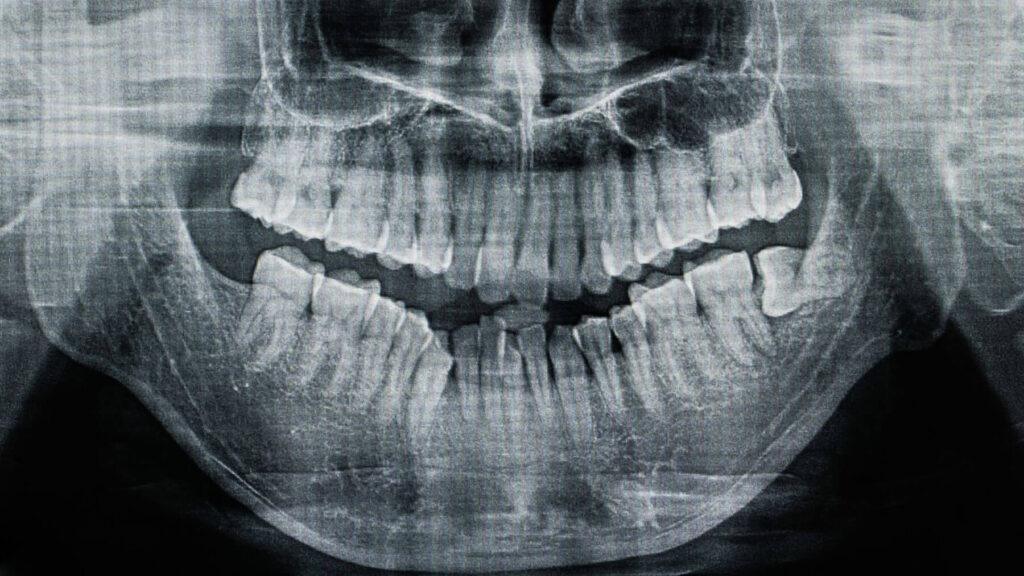

When you come to the dentist with wisdom tooth pain, our first step is to perform a thorough examination and take X-rays to see what is going on beneath the surface. This allows us to see the position of the wisdom tooth and whether it is impacted or causing damage to other teeth. Once we have a clear picture of the problem, we can determine the best course of action. In most cases, the most effective way to provide long-term wisdom tooth pain relief is to extract the tooth. This is a common and routine procedure that can be done right in our office. We are a team that is dedicated to providing you with the best solutions for your pain. We can even provide other services such as root canals if the pain is from an infection in the tooth.

- A thorough examination and X-rays help determine the best course of action.